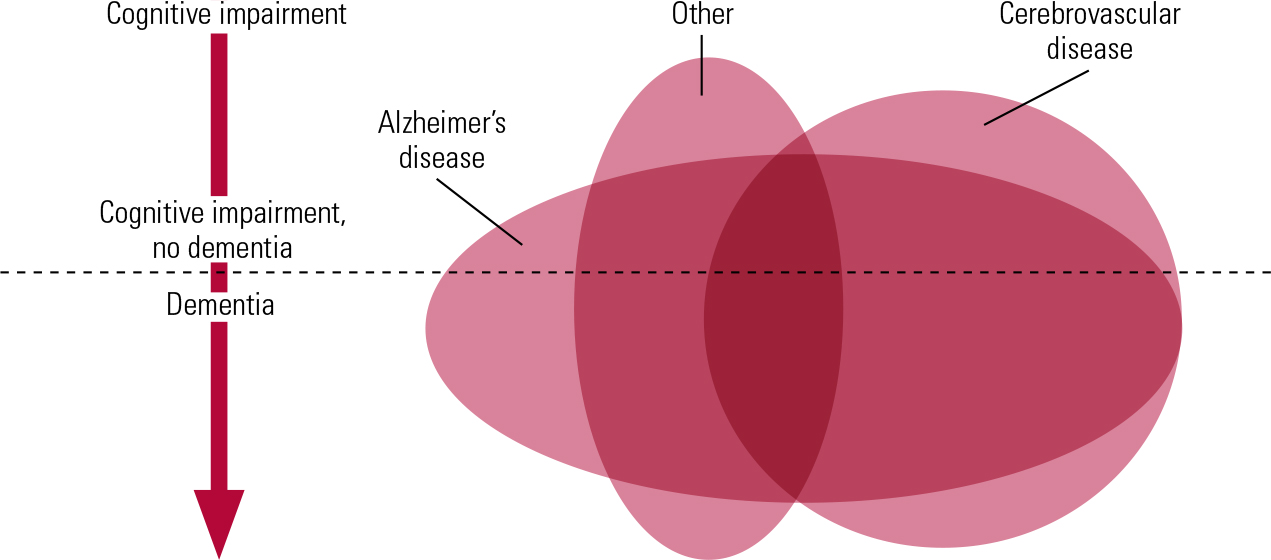

Another level of complexity in linking vascular pathology to dementia arises from the very important contribution from neuroimaging studies over the past 20–30 years. In some respects our understanding of the pathological basis of vascular dementia/vascular cognitive impairment now is at the same stage as our understanding of the pathological basis of Alzheimer’s disease was in the early 1980s. In both conditions there are complex, distinct components to the pathology (plaques and tangles in Alzheimer’s disease, different forms of vascular pathology in vascular dementia/vascular cognitive impairment) and we need to understand how these types of pathology are related and which are the key contributors to the dementia syndrome (Fig. 1). In Alzheimer’s disease we now know, following detailed clinicopathological studies (Reference Nagy, Esiri and JobstNagy 1995), that tangles correlate closely with the severity of dementia but we are at an earlier stage of discerning which of the forms of vascular pathology are the critical ones. We need this knowledge if we are to take steps to prevent vascular dementia/vascular cognitive impairment.

FIG 1 Schematic diagram showing the extensive coexistence of different types of pathology in many individuals and the correspondingly low frequency of pure forms of pathology. The degree of cognitive impairment increases from top to bottom of the diagram, and the horizontal line represents the point at which impairments are sufficiently great to be classified as dementia. ‘Alzheimer’s disease’ and ‘Cerebrovascular disease’ indicate pathology, not necessarily with dementia syndrome. ‘Other’ includes many forms of pathology that can give rise to cognitive impairment, such as dementia with Lewy bodies.